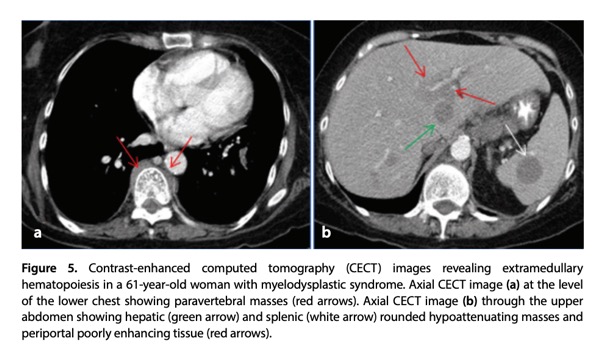

- Extramedullary hematopoiesis (EMH) refers to the production of blood cells outside the bone marrow, a phenomenon observed in patients with defective marrow synthesis (e.g., chronic myelofibrosis) or with conditions associated with peripheral red blood cell destruction (such as hemoglobinopathies and hemolytic anemias). The liver and spleen are the most common sites for EMH. Organ enlargement, particularly hepatomegaly, is more frequently observed than discrete lesions. When discrete lesions do occur, they may present as single or multiple focal masses or as infiltrative periportal or peribiliary soft tissue lesions.

Diagn Interv Radiol 2024; DOI: 10.4274/dir.2024.242826 - “On ultrasound, lesions associated with EMH can appear hypoechoic or hyperechoic and typically present as heterogeneously attenuated nodules. CT generally reveals hypodense lesions with variable attenuation and may show no, mild, or heterogeneous enhancement. In rare cases, lesions may exhibit fat density without enhancement.”